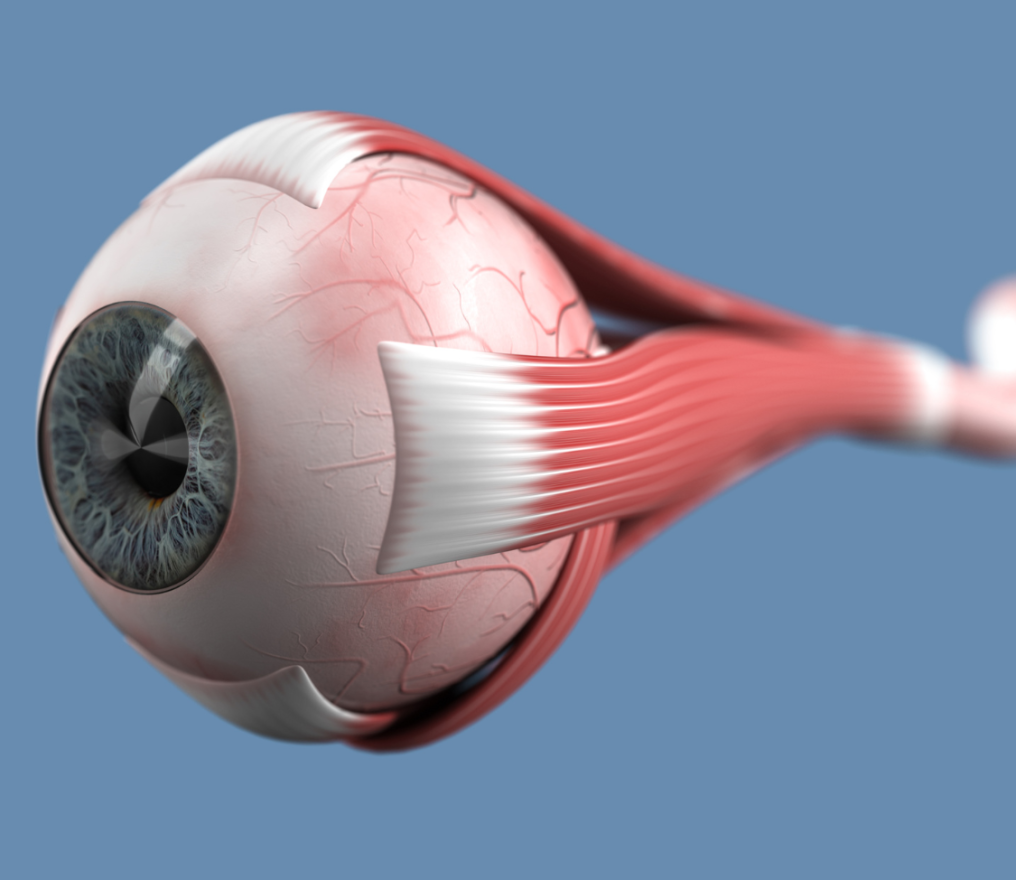

« Ressusciter » les neurones du nerf optique

Laurent Milstayn : « La rééducation oculaire a de nombreuses applications »